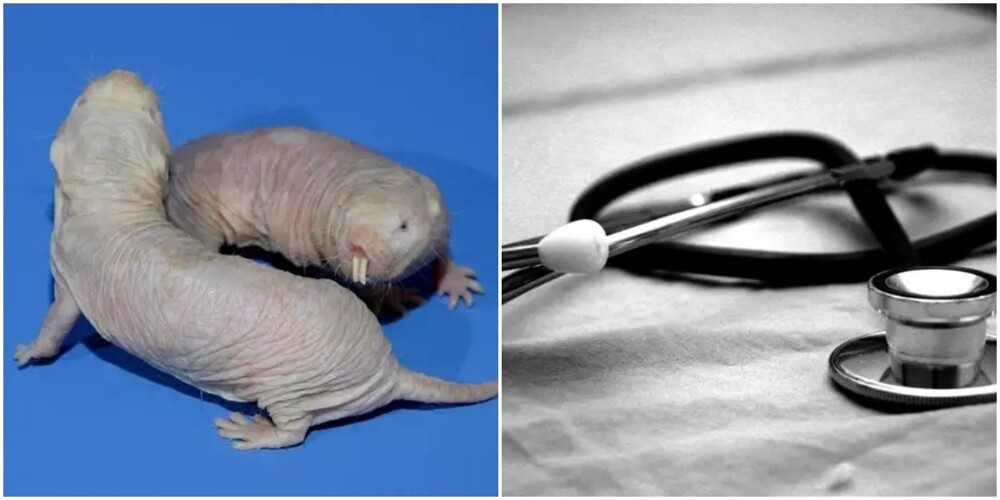

Голые землекопы могут стать ключом к долголетию человека. Учёным удалось успешно увеличить продолжительность жизни мышей, когда они обнаружили "ген долголетия" у этих лысых зверьков.